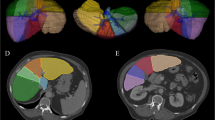

Quantitative texture analysis (QTA) of the liver was performed on abdominal MDCT scans using commercially available software (TexRAD), which uses a filtration-histogram statistic-based technique. Single-slice ROI measurements of the total liver, Couinaud segments IV-VIII, and segments I–III were obtained. CTTA parameters were correlated against fibrosis stage (F0–F4), with biopsy performed within one year for all cases with intermediate fibrosis (F1–F3).